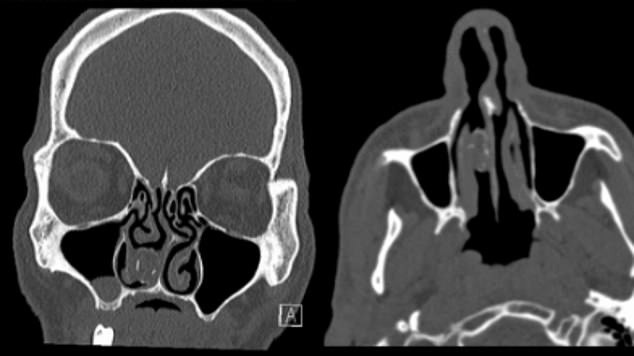

Dự án mở rộng phố Nguyễn Tuân(Hà Nội) bị chậm tiến độ, ảnh hưởng đến đời sống dân sinh. Lãnh đạo phường Thanh Xuân đang chỉ đạo quyết liệt để dự án về đích.

Thời gian hoàn thành dự kiến đến ngày 30/04/2026 nhưng hiện tuyến đường vẫn còn trong tình trạng thi công dang dở, ngập trong rác thải sinh hoạt và công trình.